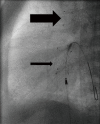

Figure 1

Newborn with hypoplastic left heart treated by Giessen hybrid approach. Lateral 90°: placing of a self-expandable 8 mm × 20 mm Sinus SuperFlex stent (OptiMed, Ettlingen, Germany) within the arterial duct (broad arrow), and an 8 mm × 18 mm Sinus SuperFlex stent within the atrial septum (slender arrow).